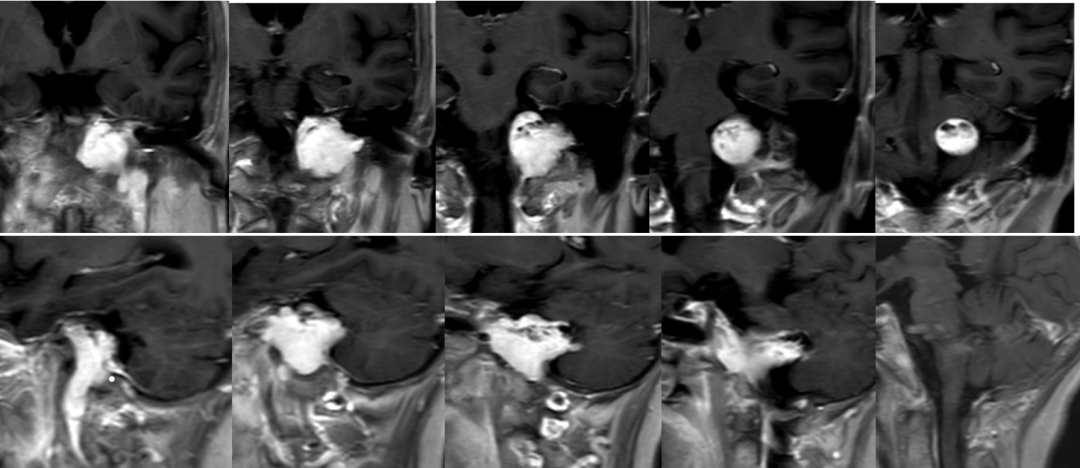

术前影像

![]()